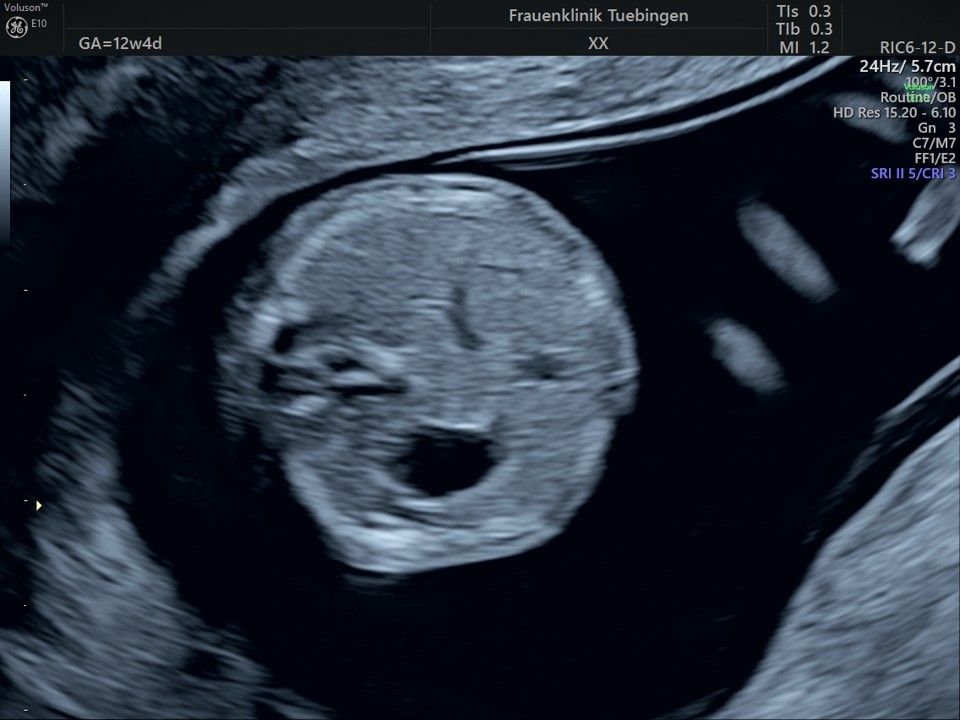

Bauchwanddefekt

Es sollte berücksichtigt werden, dass strukturelle/anatomische Fehlbildungen (z.B. angeborene Herzfehler) deutlich häufiger auftreten. Bei etwa 2-3% (1:30 - 1:50) der Feten werden Fehlbildungen gefunden. Diese können isoliert, d.h. ohne Chromosomenstörung auftreten. Sie werden aber gehäuft bei Trisomien und andersartigen Veränderung des Erbguts gefunden. Daher ist eine detaillierte Ultraschalluntersuchung im Rahmen der Risikobeurteilung unerlässlich. Sollte eine Fehlbildung erkannt werden, so ist eine Risikoberechnung für Trisomie 21 alleine nicht ausreichend. Hier sollte eher an eine Fruchtwasser- oder Mutterkuchenpunktion gedacht werden, um eine Chromosomenstörung erkennen oder ausschließen zu können.